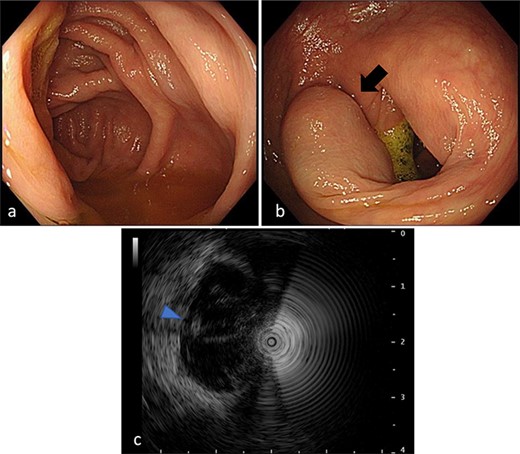

A 50-year-old man was examined at a local hospital for an annual check-up, and colonoscopy revealed an SMT-like lesion near the ascending colon. Due to this finding, the patient was referred to our hospital for further testing and treatment. He had no significant medical history or abnormal laboratory data, and physical examination findings were unremarkable. Colonoscopy confirmed the presence of SMT-like lesion in the ascending colon, while the cecum and Bauhin valve appeared normal. A cystic lesion in the intestinal wall was discovered on endoscopic ultrasonography (Fig. 1). Contrast-enhanced computed tomography (CT) also revealed the same lesion near the ascending colon, measuring 15 mm in diameter, with unclear continuity and no evidence of swollen lymph nodes (Fig. 2). Based on these findings, our preoperative diagnosis was an ascending colon SMT. Differential diagnoses included an appendiceal tumor and colon cancer. We planned to dissect the tumor for definitive diagnosis and treatment. However, endoscopic submucosal dissection is difficult for differential diagnoses.

Colonoscopy findings. (a) Total colonoscopy revealing no mucosal changes in the cecum. (b) A tumor suggesting an SMT in the ascending colon (arrow). (c) Endoscopic ultrasonography revealing a cystic lesion (arrowhead) in the ascending colon.